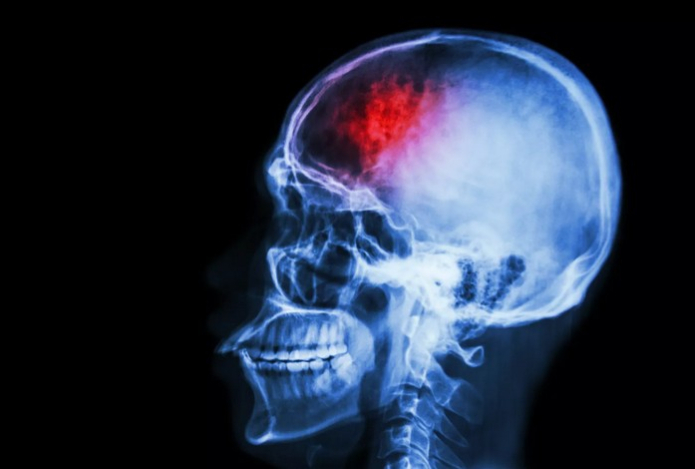

Невролог раскрыл симптомы, появляющиеся за несколько недель до инсульта

Врач-невролог Владимир Мартынов назвал тревожные симптомы, которые могут проявиться за несколько дней или недель до инсульта, сообщает Sports.kz со ссылкой на РИА Новости.

«Инсульт часто случается внезапно, но появляются первые звоночки, которые могут проявиться за несколько дней или даже недель до самого инсульта», — сказал собеседник.

Среди таких симптомов невролог назвал резкое чувство слабости или онемение в конечностях и лице, двоение в глазах, внезапная потеря или ухудшение зрения, появление затруднений в разговоре.

«Сильная головная боль может говорить об инсульте, головокружение, временная потеря координации и даже сознания..., трудности с речью могут появиться за некоторое время до инсульта», — добавил врач.